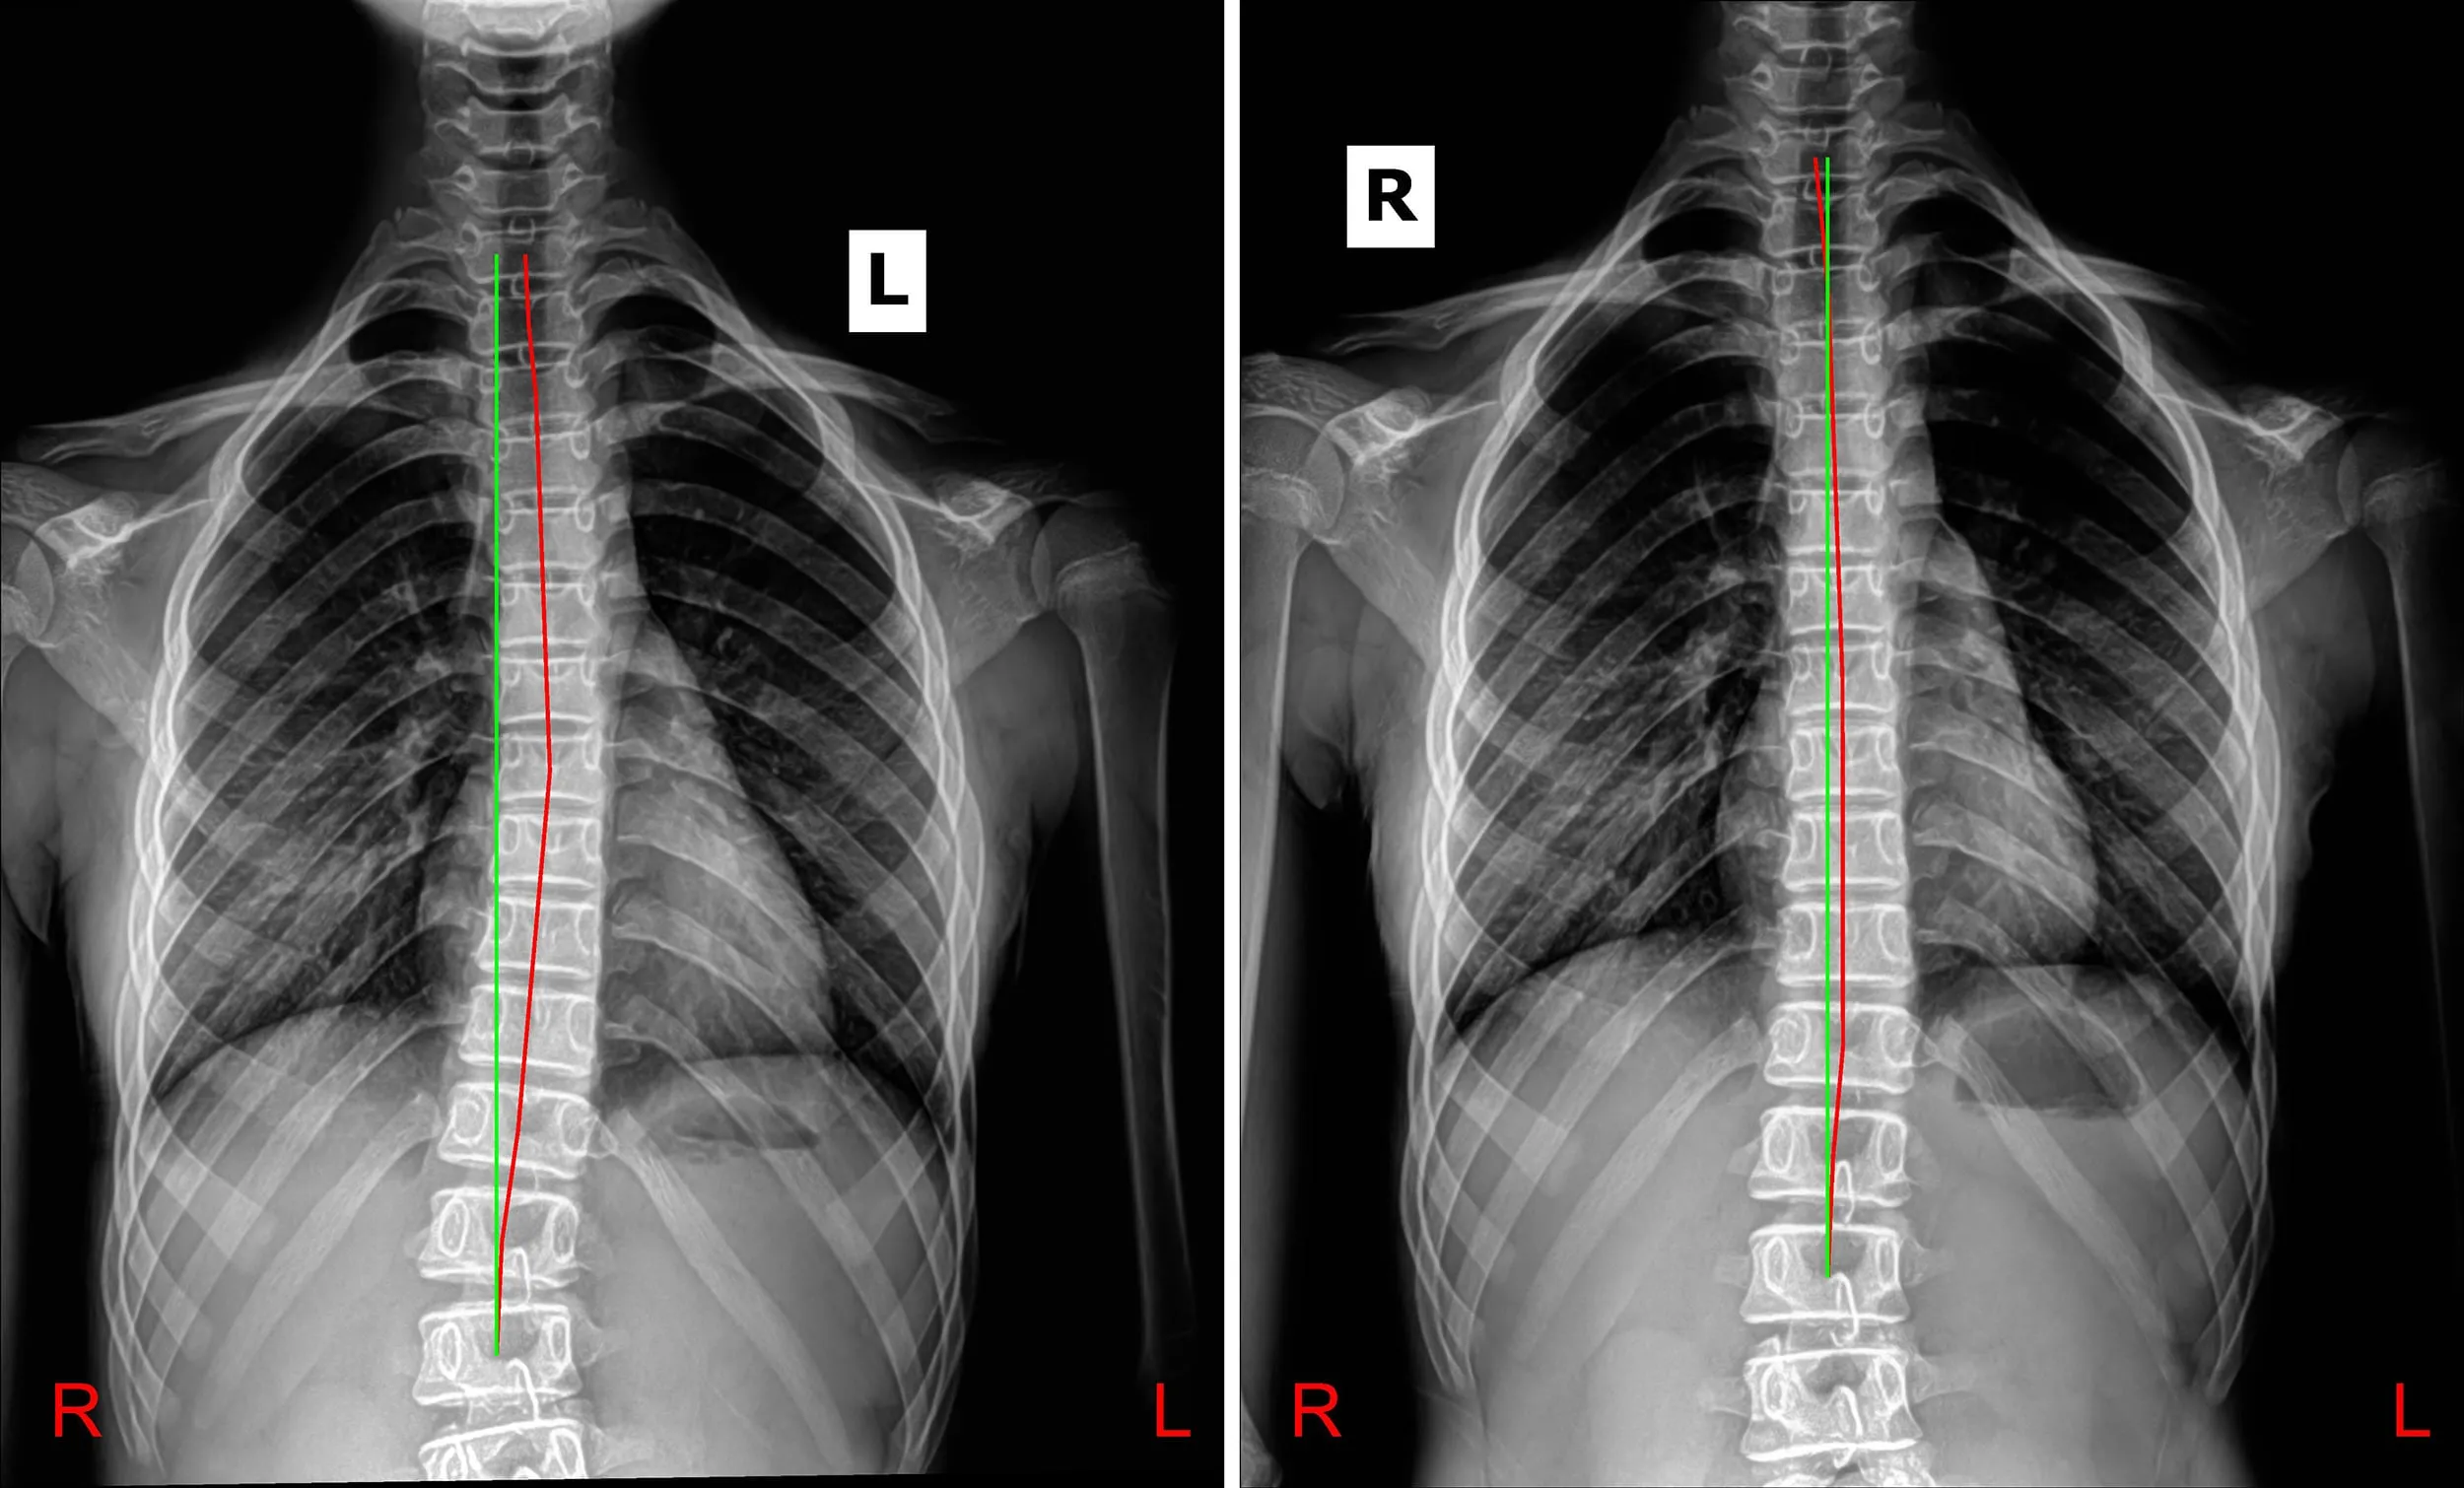

Our corrective process begins with precise postural analysis and spinal imaging to identify the degree of curve loss and the exact segmental misalignments. We then implement a customized protocol of Specific Adjustments and Rehabilitation Exercises to shift the bones, ligaments, and deep stabilizing muscles. This is the only way to achieve true, lasting postural correction and stop the cycle of degeneration.